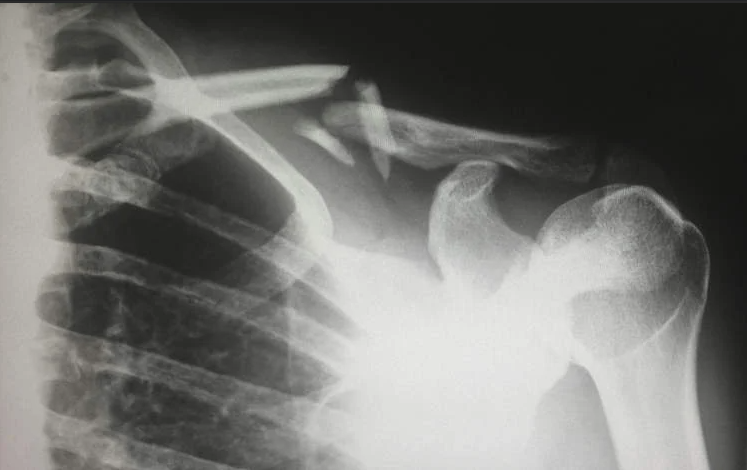

Mu Bushinwa, abaganga bo ku bitaro byitwa XinDu Traditional Medicine Hospital, biherereye ahitwa Chengdu, batunguwe no kwakira umurwayi w’umugore ufite imyaka 48, ufite ikibazo gikomeye cyo kubura Vitamin D mu magufa ye ku buryo no kwihindukiza ku buriri bituma hari amagufa avunika.